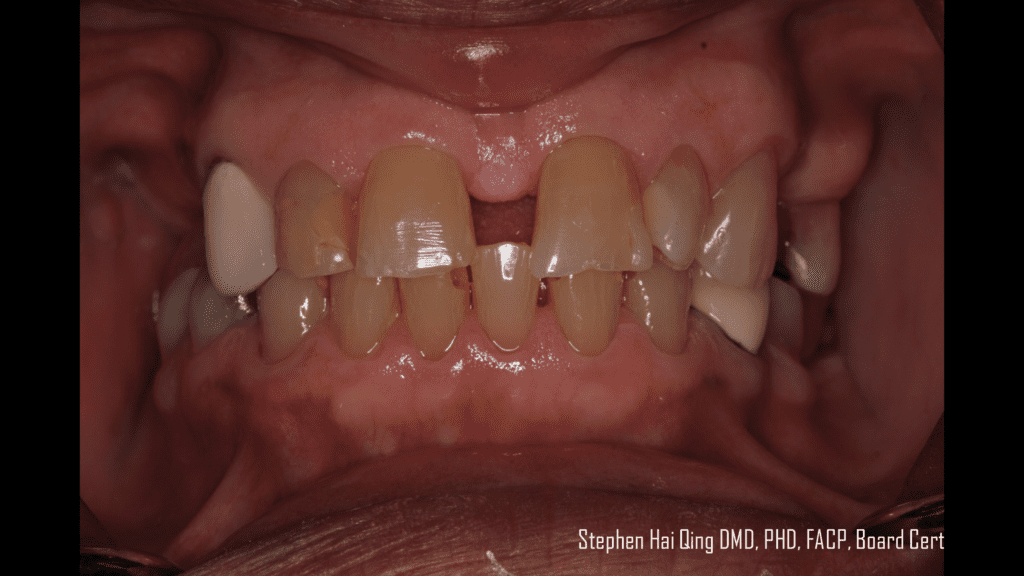

Esthetic Removable Partial Denture Posted by inception1 on August 23, 2022, 05:07 AM Esthetic Removable Partial Denture SHARE THIS POST:Share on X (Twitter)Share on FacebookShare on PinterestShare on LinkedInShare on Email « Previous Post Next Post »